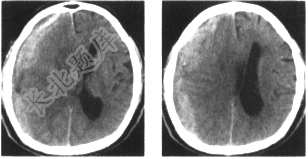

- 单项选择题男,74岁,外伤1小时,意识模糊。颅脑CT平扫如图,最可能的诊断是

A、蛛网膜下腔出血

B、脑内血肿

C、硬膜外血肿

D、脑梗死

E、急性硬膜下血肿